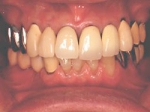

インセラム(オールセラミック)症例①

治療前治療前インセラム(オールセラミック)冠による修復。 主訴は前歯が汚い 金属を使わないオールセラミックでの治療を勧めた。 術前 治療後治療後術後

インセラム(オールセラミック)症例②

治療前治療前術前 治療後治療後術後 歯の尖端の透明感までよく再現できている。